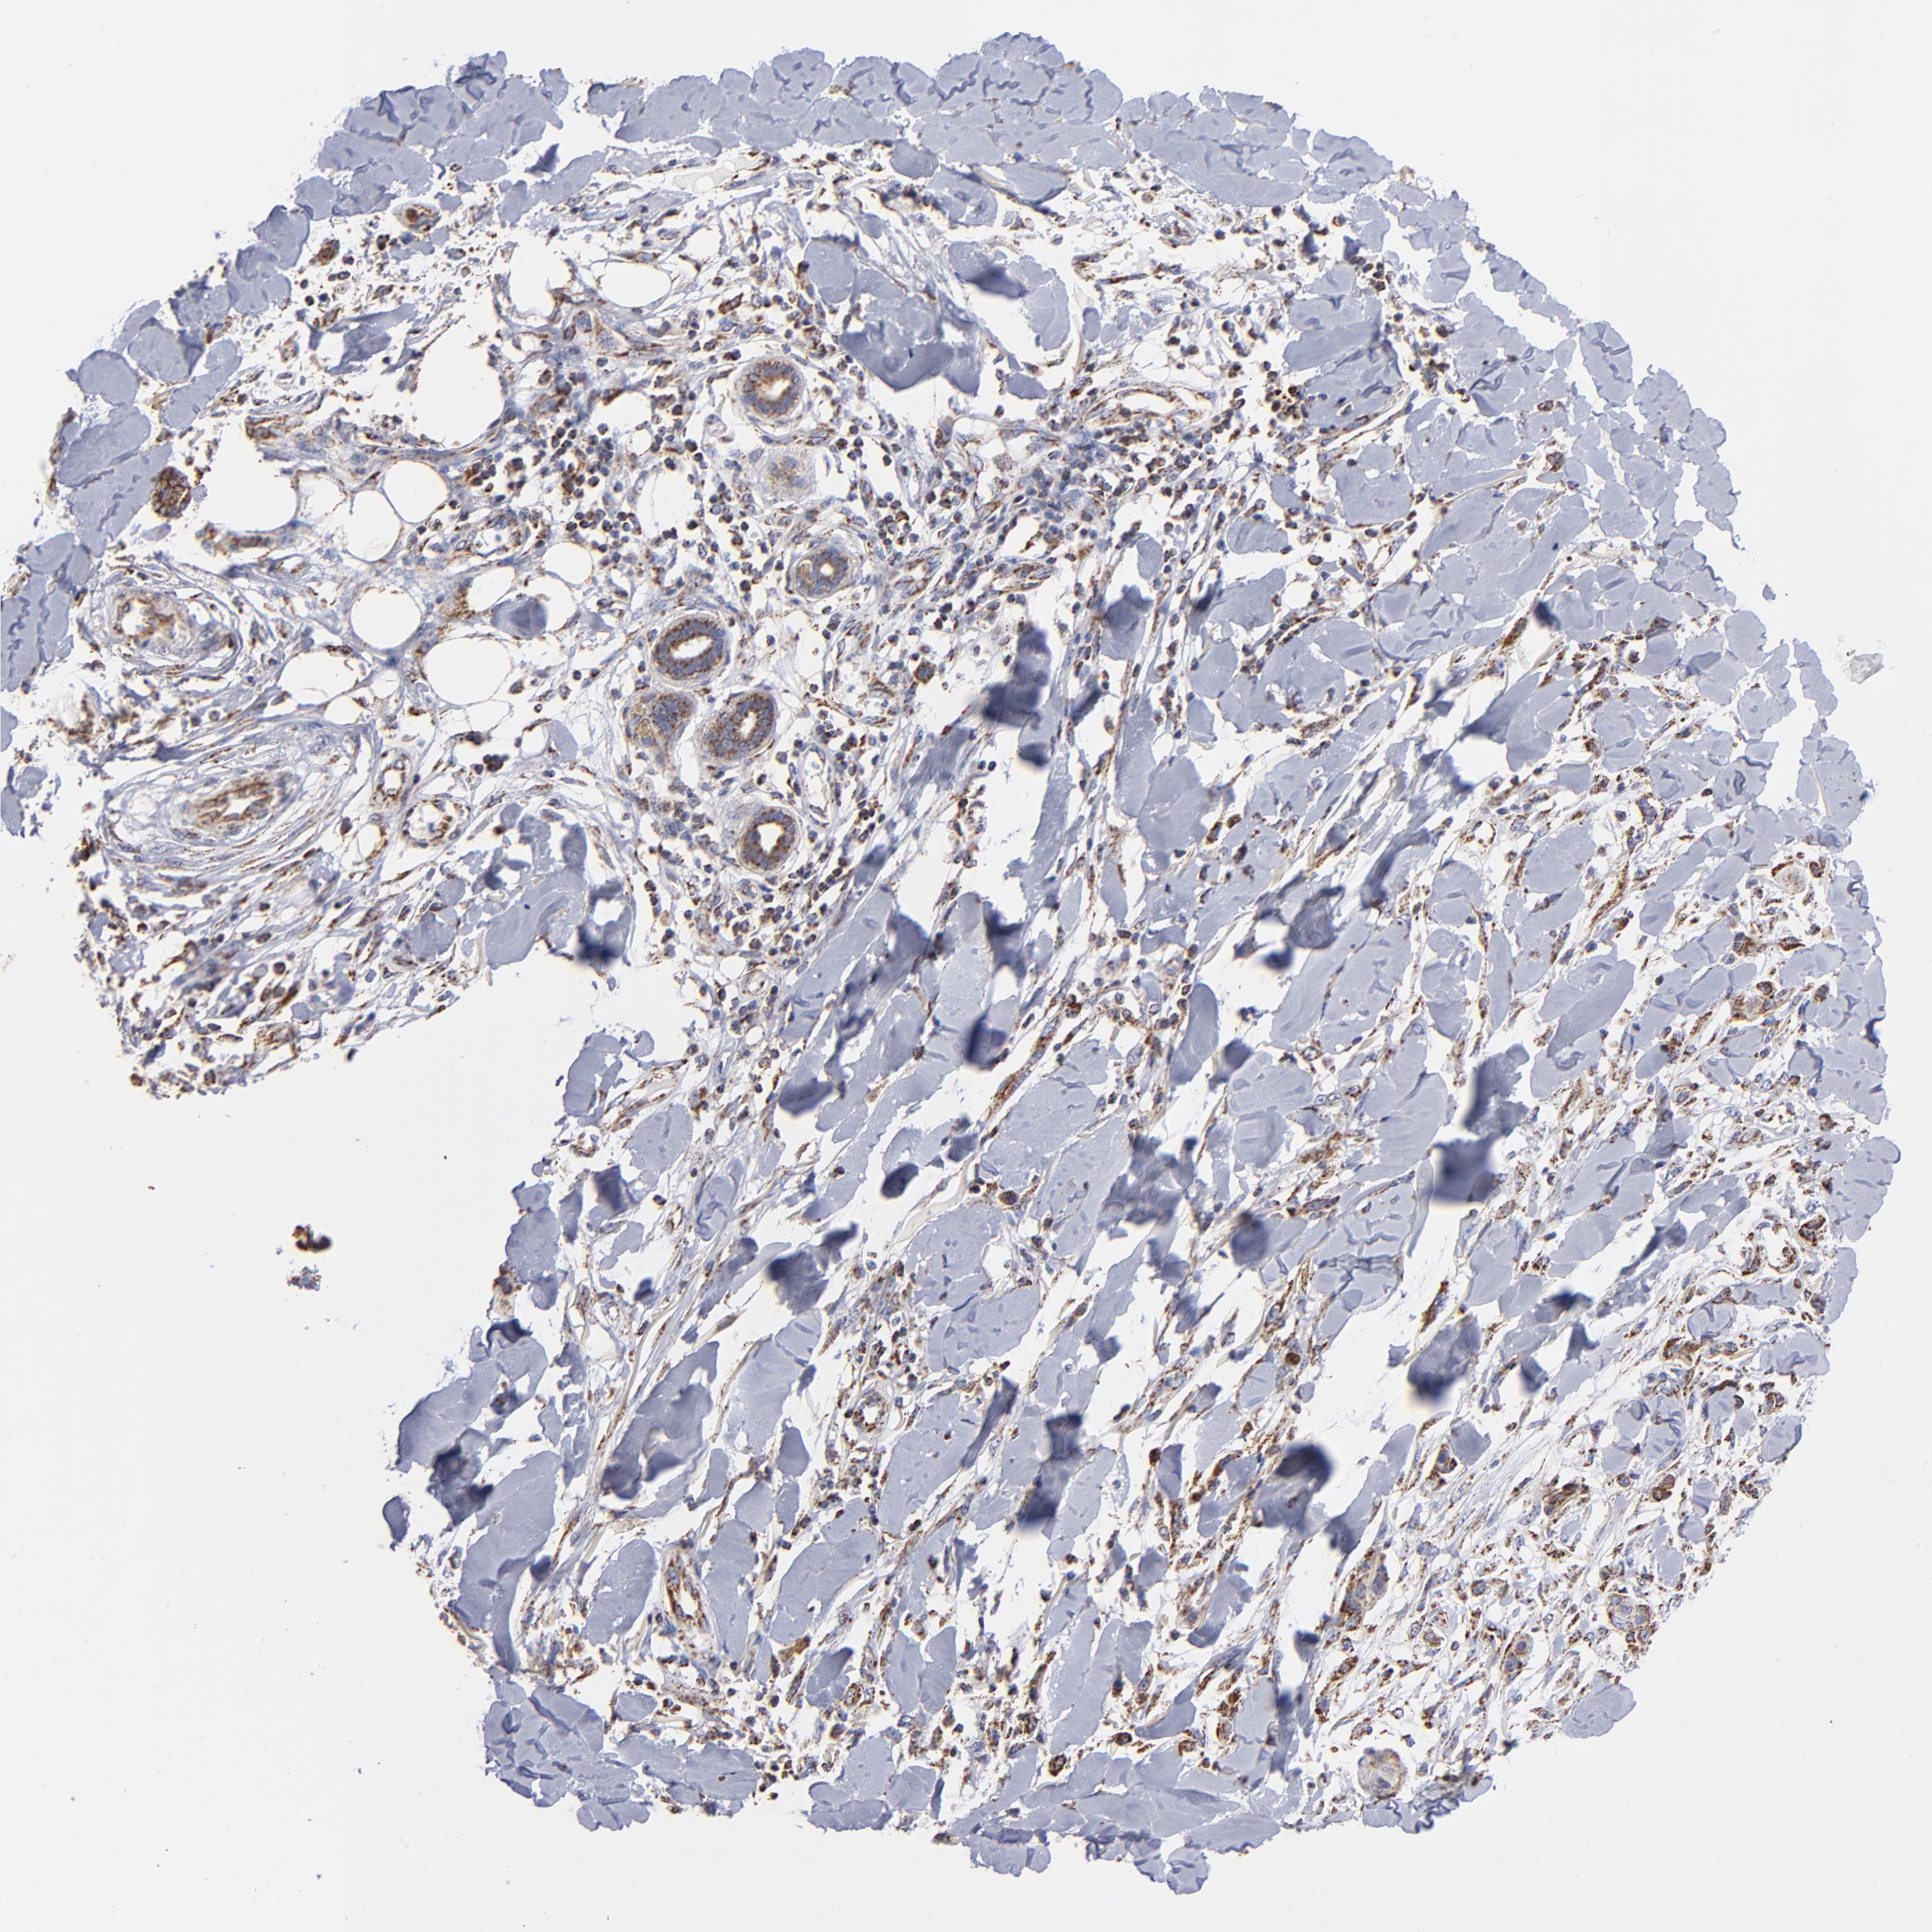

SKIN CANCER - Protein expressioni

A mouse-over function shows sample information and annotation data. Click on an image to view it in a full screen mode. Samples can be filtered based on level of antibody staining by selecting one or several of the following categories: high, medium, low and not detected. The assay and annotation is described here.

Antibody stainingi

Antibody staining in the annotated cell types in the current human tissue is reported as not detected, low, medium, or high, based on conventional immunohistochemistry profiling in selected tissues. This score is based on the combination of the staining intensity and fraction of stained cells.

Each image is clickable and will lead to virtual microscopy that enables deeper exploration of all samples and also displays staining intensity scores, fraction scores and subcellular localization as well as patient and tissue information for each sample.

Antibody HPA003280

Staining

High

Medium

Low

Not detected

Intensity

Strong

Moderate

Weak

Negative

Quantity

>75%

75%-25%

<25%

None

Location

Nuclear

Cytoplasmic/membranous

Cytoplasmic/membranous,nuclear

Squamous cell carcinoma, NOS

Basal cell carcinoma